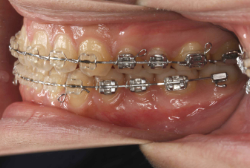

「乳歯が生え替わらない」という主訴で来院したケースです。 診断の結果、「左上永久犬歯が第一小臼歯後方上部に埋伏しているため、左上乳犬歯が晩期残存している症例」と判明しました。

このような症状の場合は、手術で埋伏している永久歯に金具を取り付け、矯正装置で牽引する必要があります。同時に凸凹の解消と前突した前歯を内側に入れるために上下左右の小臼歯を抜歯させて頂くことといたしました。

この方の場合は、マルチブラケット装置にて治療を開始し、治療期間2年3ヶ月で終了しました。犬歯の牽引距離が非常に大きかったため当院の平均治療期間よりも大幅に期間がかかりましたが、埋伏犬歯を完全に正しい位置まで誘導することができました。同時に 前歯の前突と配列の凸凹も解消しました。

このような症例は、成人してしまうと埋伏歯の反応性が悪く、あまりにも動きが悪い場合は牽引をあきらめて抜歯する場合もあります。歯科医院の検診で親知らず以外の埋伏歯を指摘された場合は、できるだけ早く矯正専門医に御相談下さい。